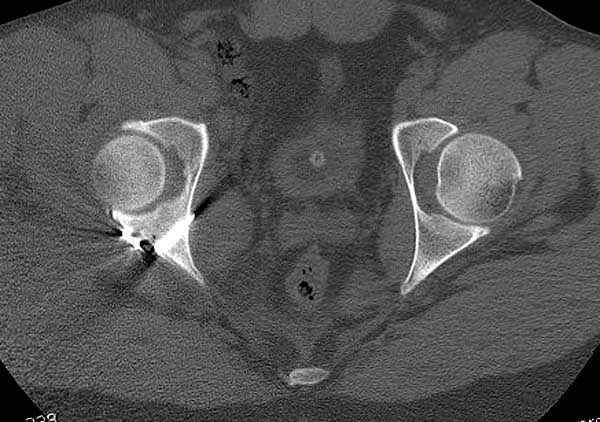

11:50 больной в послеоперационной, рентгенограмма N7, компьютерная томограмма в тот же день N8-10

Через 48 часов первая перевязка, пареза седалищного нерва нет, удаление дренажных трубок Начало физиотерапии, движение в суставе до 30 градусов сгибания и до полного разгибания, вставание на костыли без нагрузки, назначение Indocin по 25 мг три раза в день для профилактики гетеротопической оссификации.

Третий день Послеоперационная рана сухая, назначена профилактическая доза (тромбоз) Lovenox 30 mg. Перед выпиской доплер сосудов нижных конечностей. Выписан, продолжение физиотерапии и явка на осмотр через две недели.